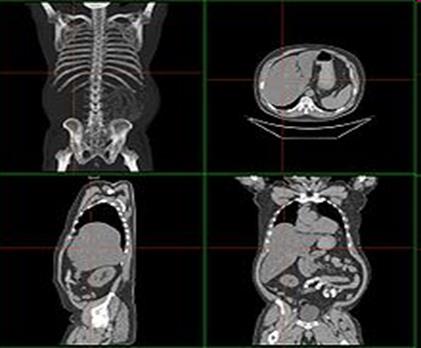

4. В распознавании нефролитиаза помогает анамнез (наличие приступов почечной колики с характерной иррадиацией боли, отхожденне с мочой конкрементов и др.).